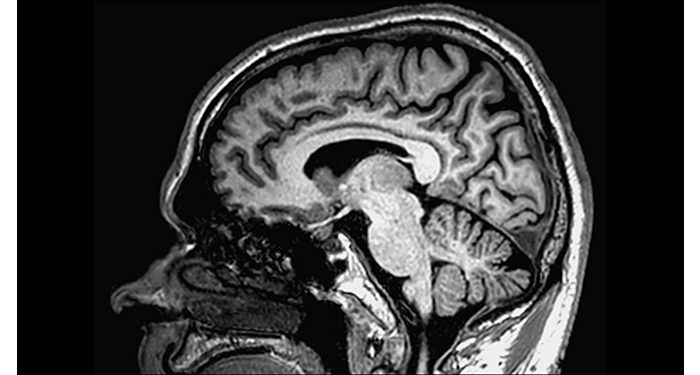

70% of radiologists consider neuro indications to be challenging, mostly due to a lack of appropriate imaging and visualization techniques¹. Philips aims to provide the best possible diagnostic clarity and treatment guidance for all patients with neurological disorders. By leveraging our dStream digital platform, this year, we are introducing, a set of novel imaging and visualization strategies. These may empower you to resolve complex neuro questions with more certainty, as well as unlock new neuro territories in advanced Neurofunctional applications. This is a key step towards elevating neuro diagnostics and ultimately touching more lives with MR imaging. ¹ TMTG Market Survey 2016

New neuro applications

Take a look at our other neuro applications